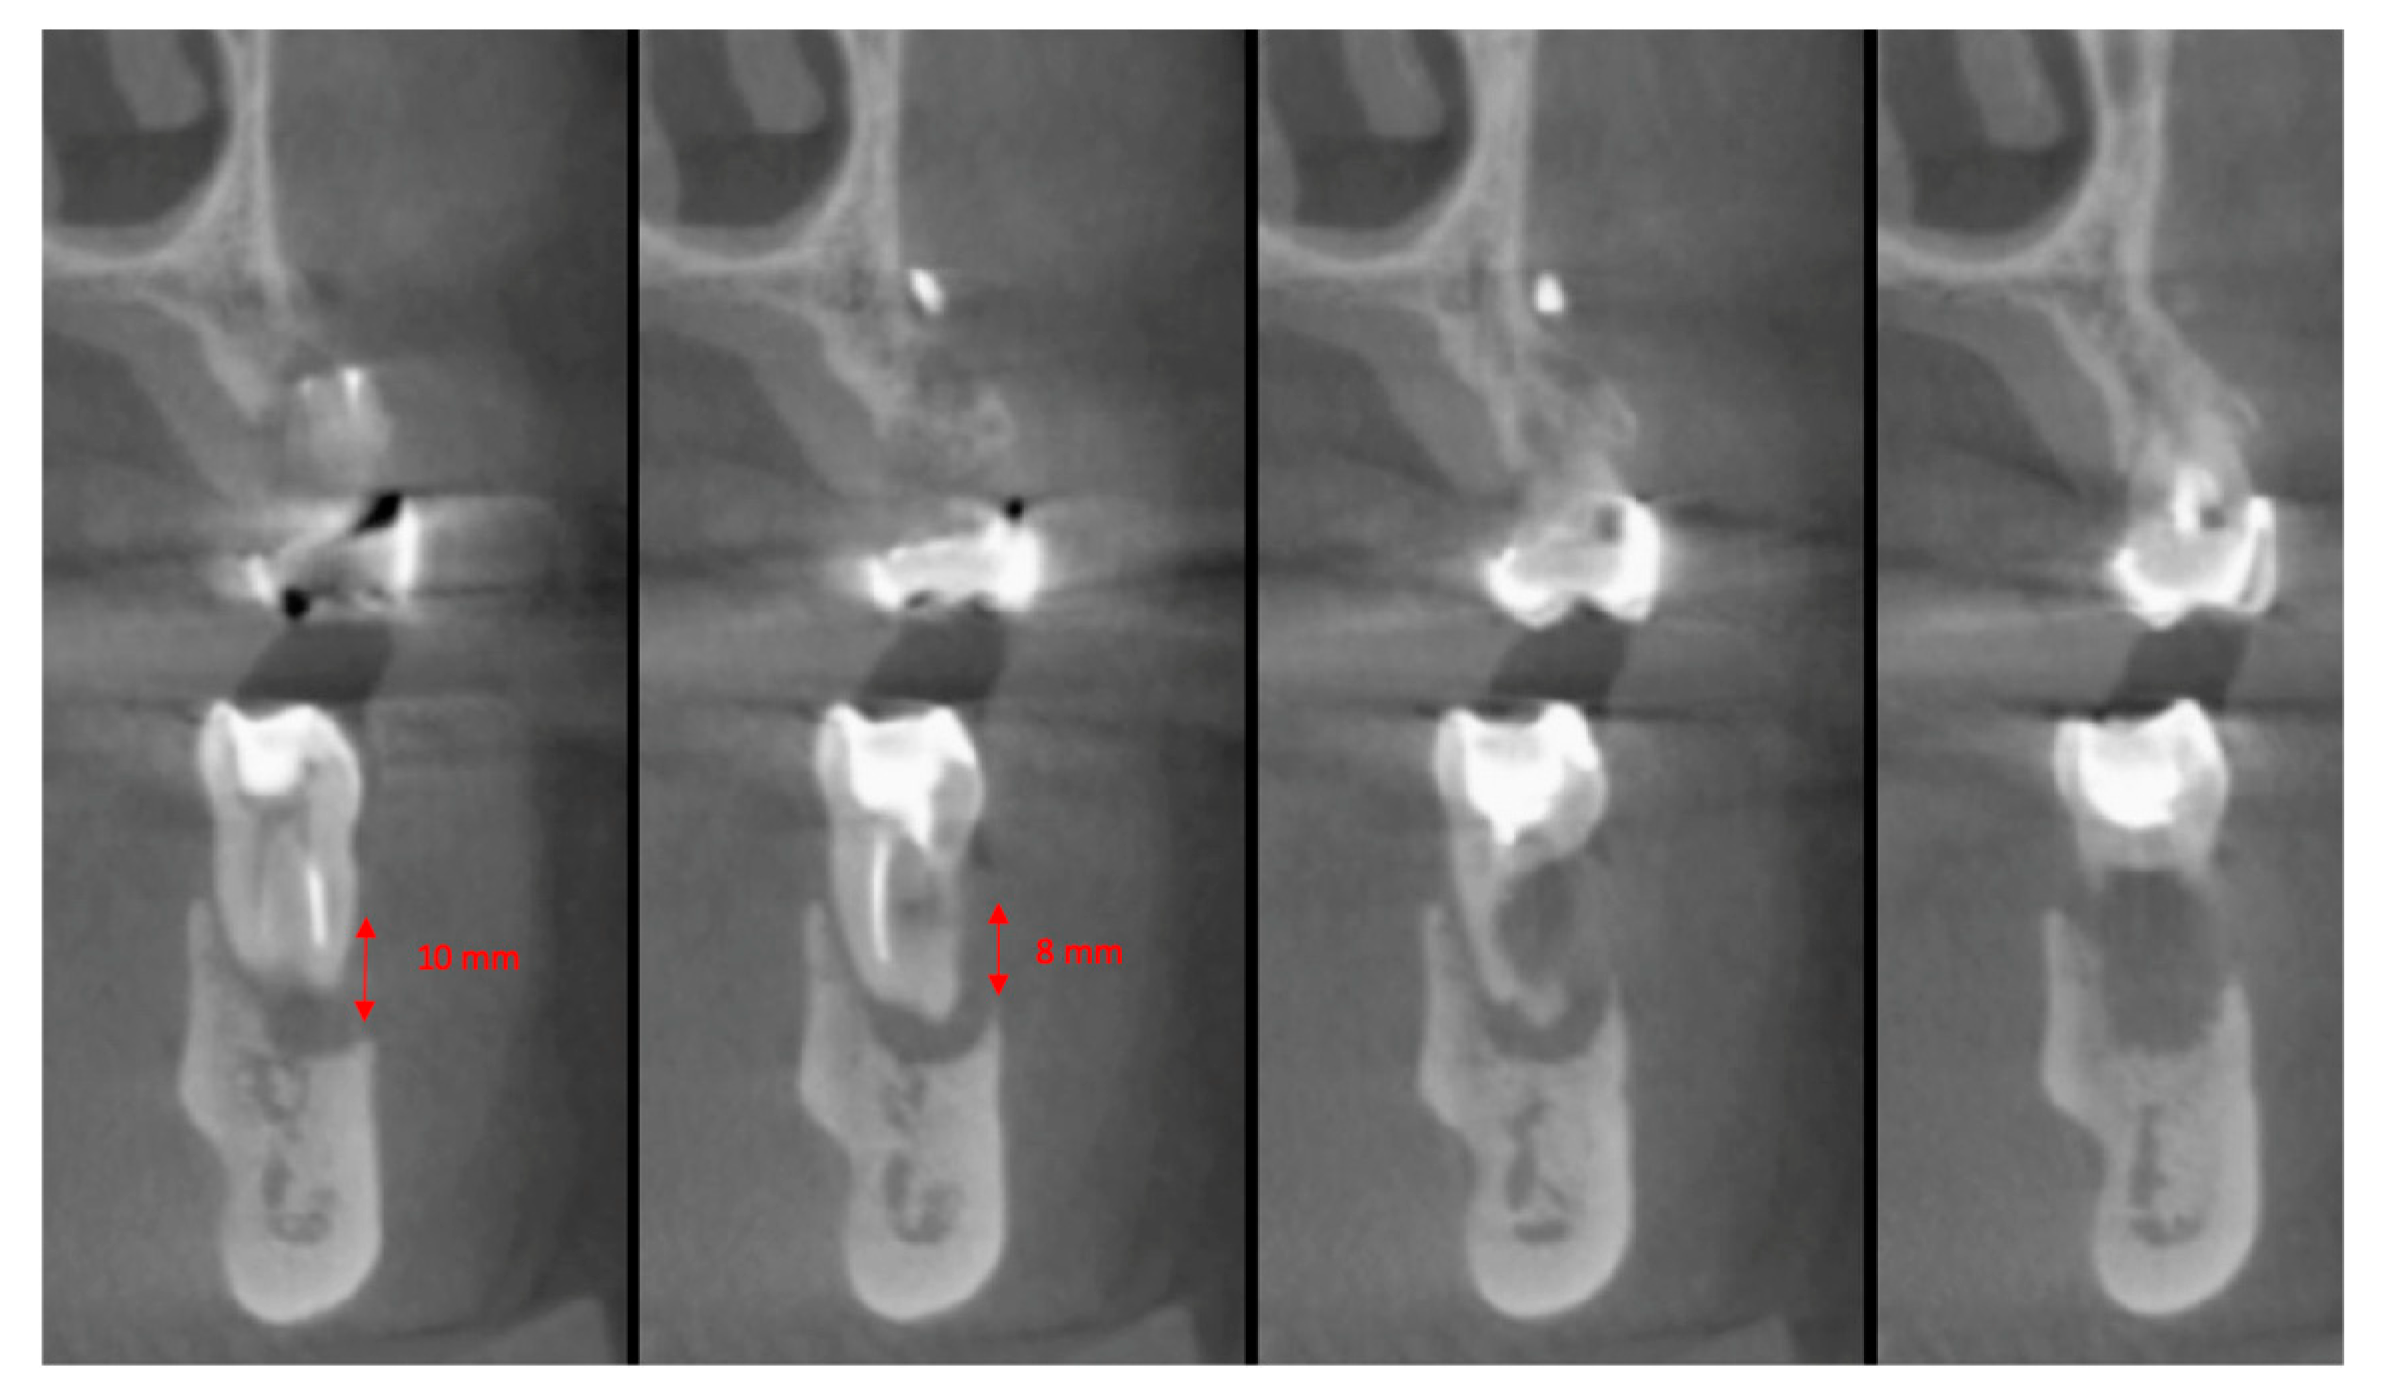

The vertical average defect was 9.16 mm, buccal lateral/palatal 7.0 mm, and mesio-distal 10.3 mm. The measurements were intraoperatively performed with a millimeter periodontal probe. The endodontic material mechanically cleaned before the tooth was placed inside the Tooth Transformer device. The endodontic material was removed using a drill bur with the attention to cut the canal in excess with the aim to remove all the cement. No surgical complications were registered. Pre and post-operative X-rays (section from CBCT) were collected from the same case (Figure 1, Figure 2, Figure 3 and Figure 4). After four months, 13 histological and histomorphometrical evaluations were performed (Figure 5). The Bone Volume/Total Volume average (BV%) was 41.47 (S.D. ± 11.51), the Residual Graft/Total Volume average (Graft%) was 16.60 (S.D. ± 7.09), and the Vital Bone/Total Bone average (VB%) was 21.89 (S.D. ± 9.72). No extraneous material (gutta-percha or cement) was detected in all samples (Table 3).

Figure 2. In the cbct section in zone 36, it is possible to note the bone loss dimension.

Figure 3. The cbct section in zone 36, two months after the Guided Bone Regeneration (GBR). The defect was completely filled using the endodontical treated elements site 3.5 and 3.6 (Italian teeth numeration).

Figure 4. The cbct section in zone 36 after the implants healing, six months after the GBR.